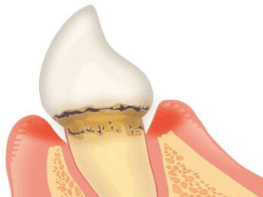

【中等度歯周炎】

歯槽骨が溶けて後退

【重度歯周炎】

歯槽骨で歯を支えられなくなる

歯肉の炎症が更に進んでいき、歯周病菌が顎の骨にまで達してしまい、歯槽骨が溶け始めます。歯周ポケットが深くなり、歯がグラグラし始めます。歯肉からの出血だけではなく、歯と歯肉の間から膿が出る事もあります。

重度になると更に症状が進行し、顎の骨が半分以上溶けています。歯周ポケットが更に深くなり歯ぐきが退縮して歯のグラつきが悪化します。歯肉からは膿が出るので口臭がきつくなり、治療せずに放置していると最終的には歯が抜け落ちる事もあります。